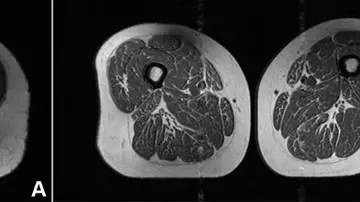

Studi MRI menunjukkan dampak buruk makanan ultra-proses pada lemak otot, meningkatkan risiko obesitas, diabetes, dan osteoarthritis.